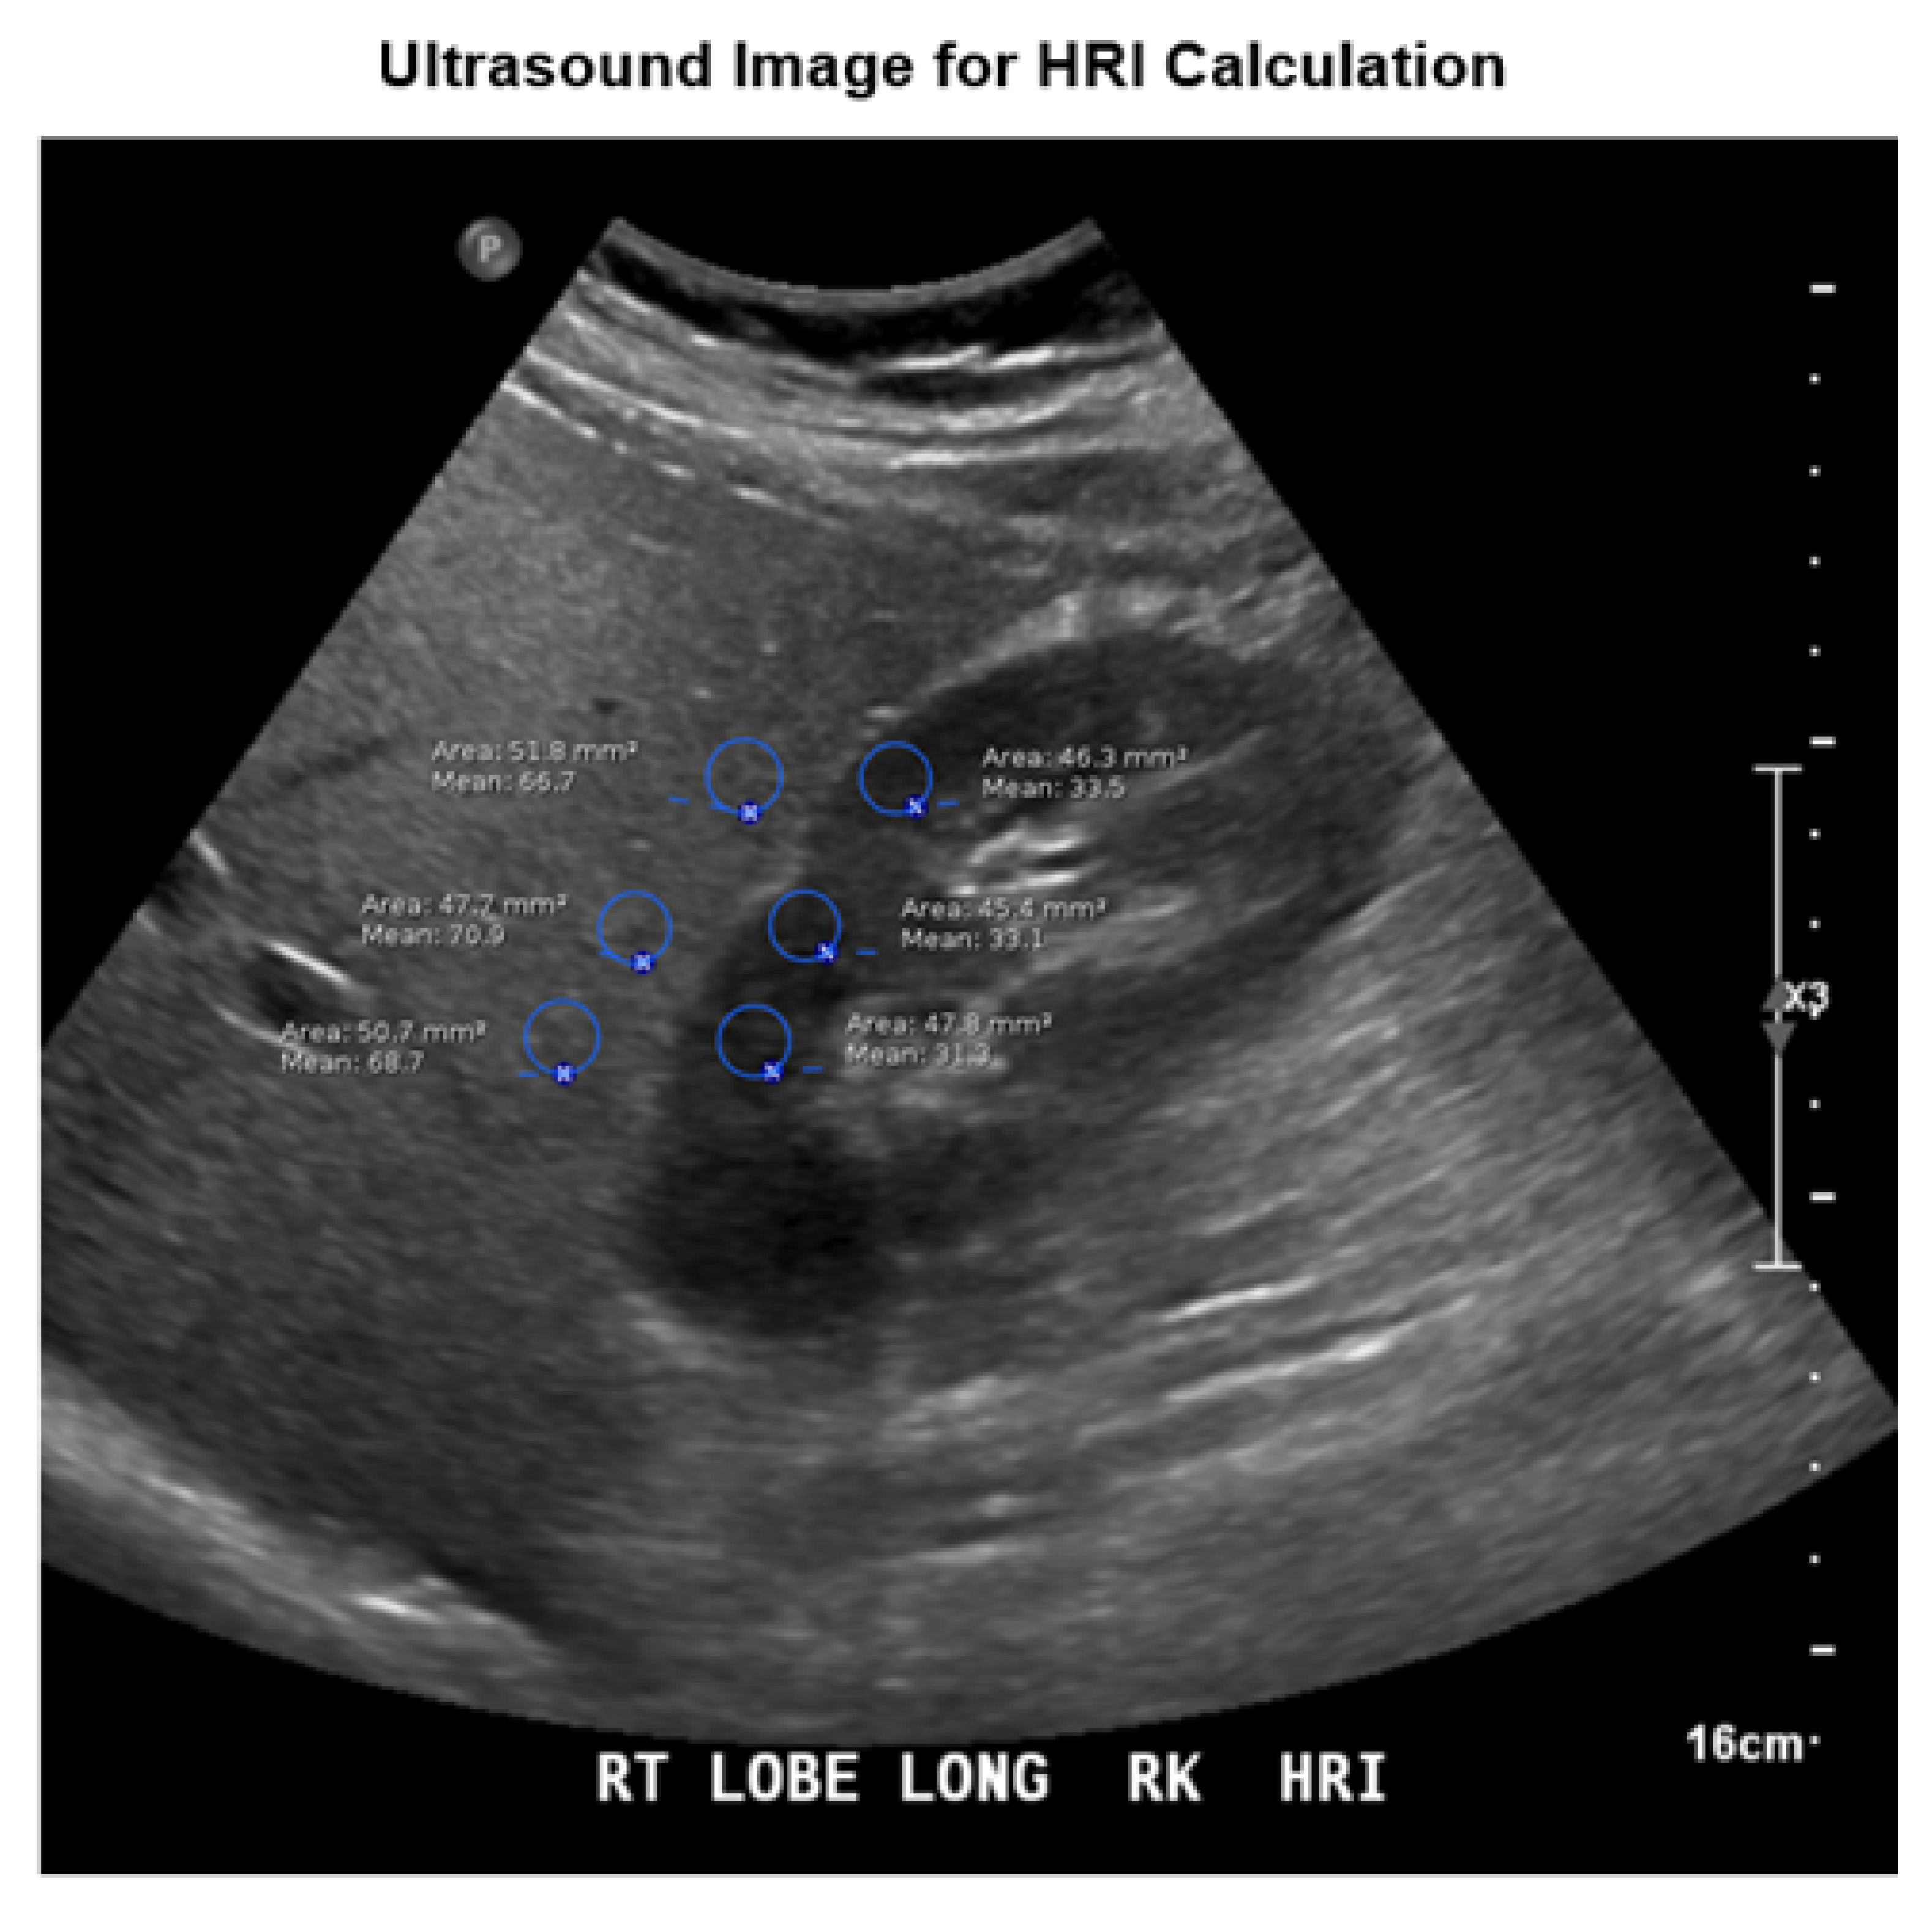

2.4. Image Analysis and HRI Calculation